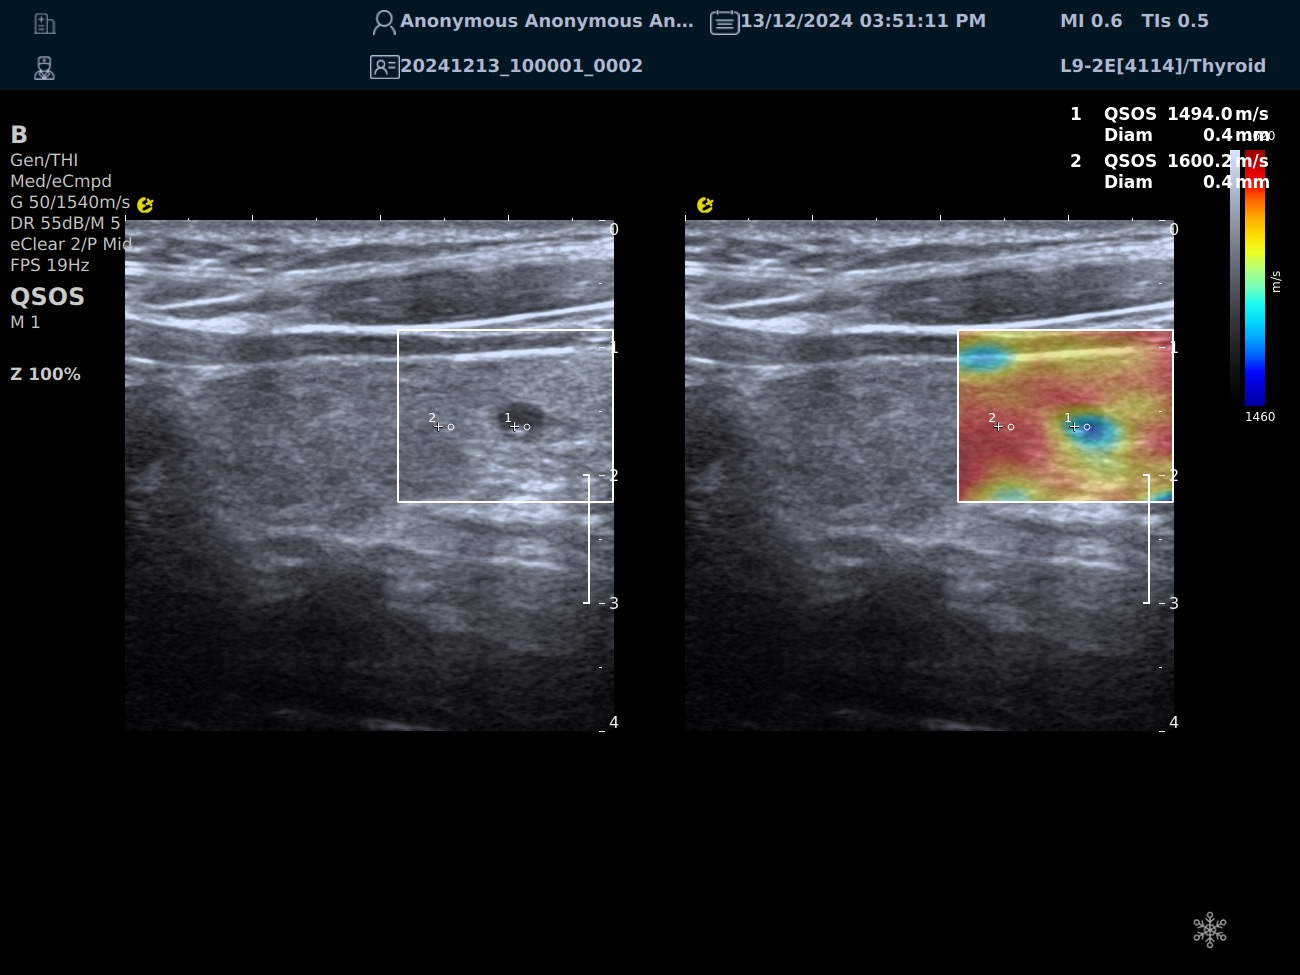

QSOS声速定量成像

测量原理

QSOS声速成像技术利用声波在组织中的传播速度差异性,计算不同位置的声速值,反映组织的物理特性。

成像过程

利用超声探头发射超声波脉冲,分析反射信号的时间延迟,确定声波传播路径和速度,构建声速分布图像。

图像显示

QSOS技术采用彩色编码显示声速图像,不同颜色代表不同声速值,便于医生识别病变部位和测量。

25fb8cb17586b86e5d915a2be3025a2.png

技术优势

?精准定量反映组织特性,成像更敏锐?彩色编码直观显示,轻松发现异常?捕捉声速差异,早期、微小病变更易察觉

肌骨22.png

肌骨领域的应用

?精准定位损伤部位?判断损伤严重程度?监测肌肉营养?评估肌少症?骨质疏松评估